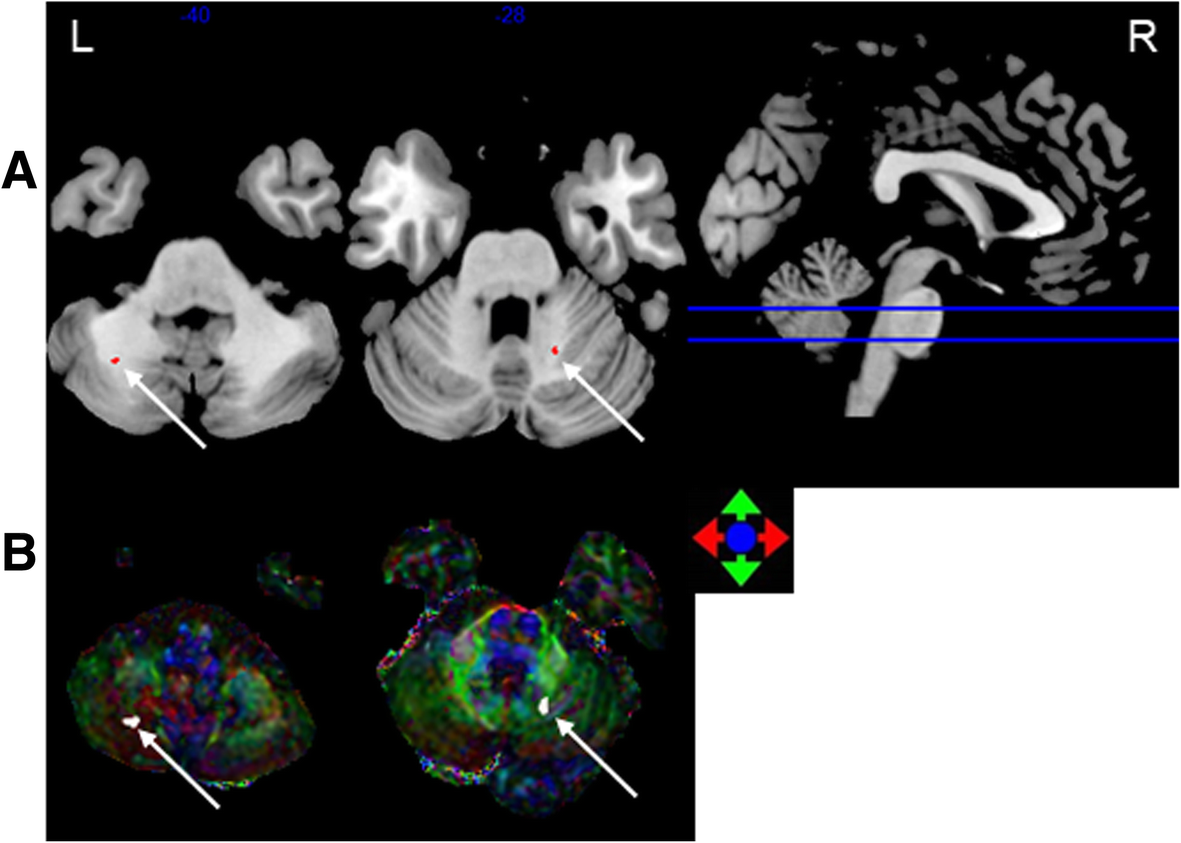

Fig. 1

The most discriminating voxels for the classification of 0–6 months post-RT versus control; the image is the cutaway view: a displayed on the mean group fractional anisotropy (FA) map, the abnormal regions are shown in red; b FA map displayed in color (Red represents the left and right direction, green represents the up and down direction, and blue represents the front and rear direction). The left side of the brain is on the left side of the image. L = left, R = right